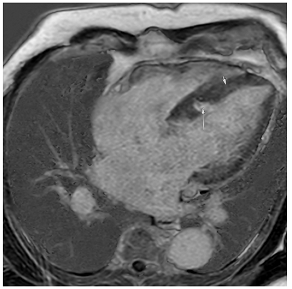

Table 3 summarises a suggested CMR scan protocol for the diagnosis of presumed HHD and differential diagnosis of patients with a “thickened left ventricle”.

Table 3.

The cardiovascular magnetic resonance protocol used for assessment of hypertensive patients. The described protocol can be acquired within 45–50 min. Images are examples from patients with hypertensive heart disease.